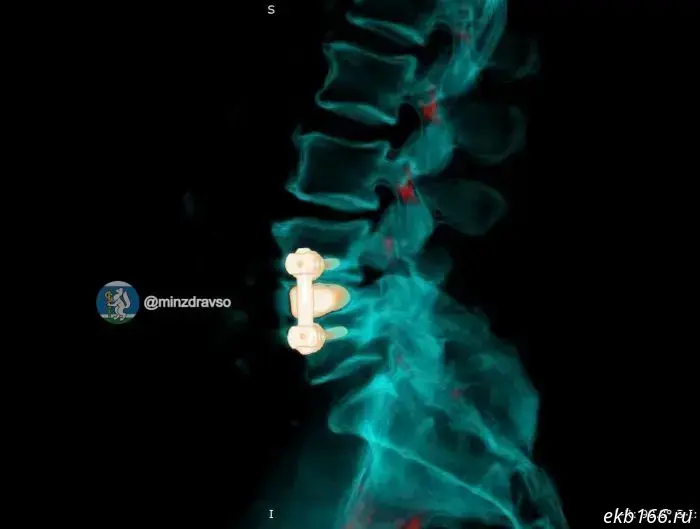

The man's problems began after a long-ago operation on the lumbar spine. His body began to reject the previously implanted metal construct, a peri-implant infection developed, and the patient's condition deteriorated rapidly. First the neurosurgeons removed the infected construct and debrided the focus of inflammation. The patient then underwent a course of intensive antibacterial therapy and preoperative preparation. Subsequently, a titanium 3D implant manufactured according to his individual anatomical parameters was implanted, and spinal fixation was performed using Russian cancellous screws.